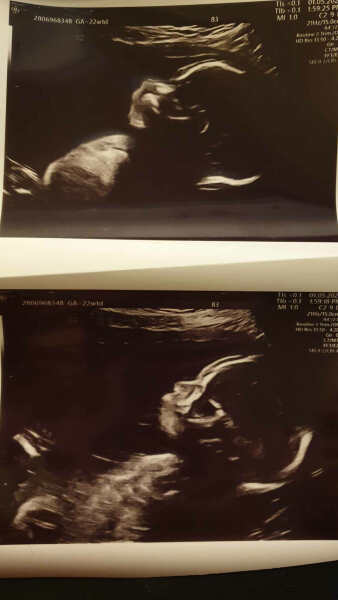

Had both a midwife and scan appointment today as at last scan wee man was refusing to cooperate with the sonographer so she couldn't get a good look at his heart - Thankfully all is well and wee man was quite the show off and poser for her today!!

Textbook perfect scan for getting a good look at everything she said, she was very happy with the wee dude <3

I got some super cute wee pictures of little man today so thought I'd share - I also got to hear his heartbeat for the first time which was so so nice to hear, I got to record it too which I was thankful for!